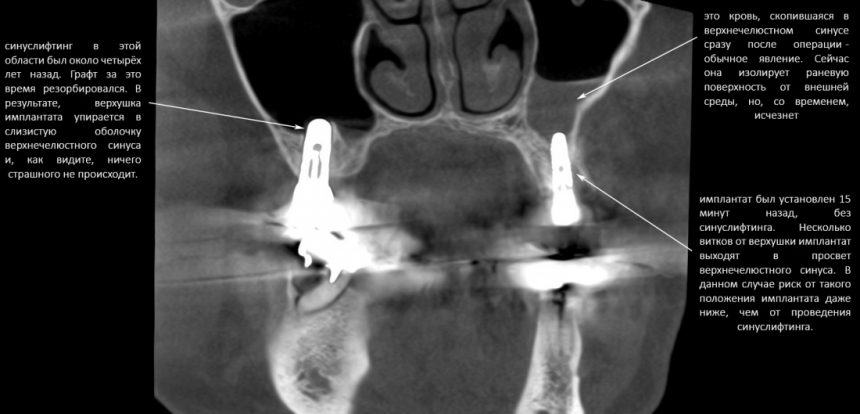

Для этого мы сделали КЛКТ:

И КЛКТ показала нам, что с имплантатами и окружающей костью всё зашибись. Через 12 лет после операции, отсутствия наблюдения, пофигизма в замене временных коронок! Нужны ли тебе еще какие-нибудь доводы в пользу долгосрочной эффективности метода?